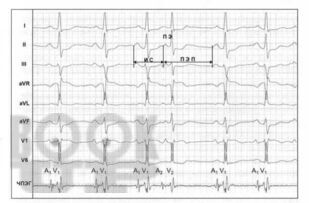

В учебном пособии дано определение суправентрикулярных нарушений ритма сердца, изложены современные представления по этиологии, патогенезу и распространенности данного вида аритмий сердца. Имеются тестовые задания и ситуационные задачи для самоконтроля знаний, издание иллюстрировано рисунками, схемами и таблицами. Учебное пособие предназначено для ординаторов, обучающихся по специальности 31.08.49 Терапия и слушателей дополнительного профессионального образования.